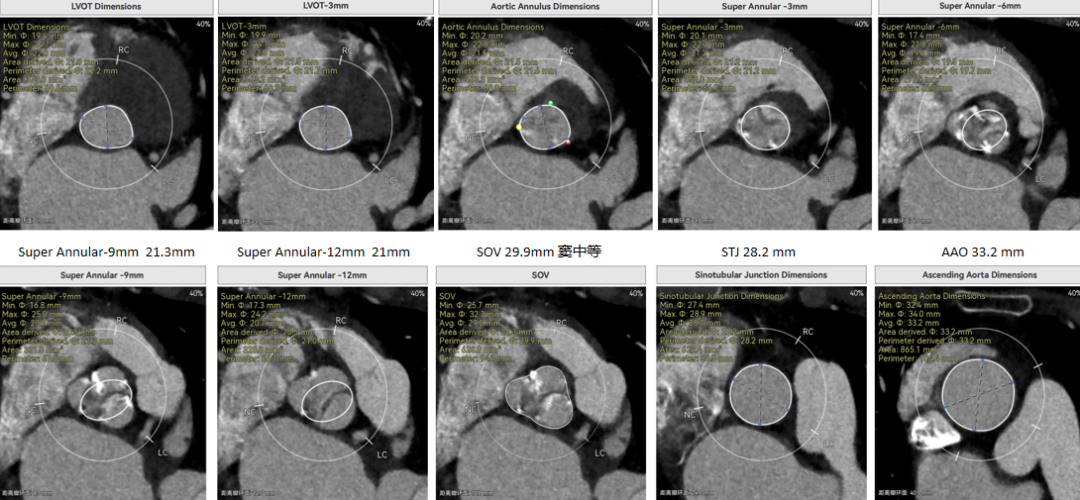

修建成教授 南方医科大学南方医院(点击查看专家详细简历) 细微之处防未然,创新携手寸寸安: 愈知临床无小事,任何风险的蛛丝马迹,都可能牵动全局。我常对团队说,真正的严谨,是将所有潜在 scenario 视作必然,在术前便一一拆解、化解 —— 如同在堤坝溃决前便筑牢每一寸基石,让风险连萌芽的机会都没有。 此次应用全球首创的预装干瓣,是基于对患者的综合考量,拥抱创新,实践创新,让创新携手助力“万全之策”的重要环节。 术前推演需要结合器械的特性:深度了解才能得心应手,结合患者基础病的相互影响并落实到术后 72 小时的并发症预警,每个环节都要像精密齿轮般咬合无误。这份 “穷尽万一” 的准备,从来不是对完美的苛求,看似耗时费力,实则是对生命最质朴的承诺 ——以医者的周全,携手创新的产品,为患者的万无一失不断努力! 患者病史 因 "反复胸闷伴活动后呼吸困难 3 年" 入院:患者 3 年前无明显诱因反复出现胸闷,部位在前胸,有憋气感,间有心悸,伴有活动后呼吸困难;外院就诊,查心脏彩超示 "主动脉狭窄、二尖瓣关闭不全"; 既往有高血压 20 余年,长期服用氨氯地平阿托伐他汀钙片降压治疗;有糖尿病 1 年,长期服用二甲双胍、阿卡波糖降糖治疗。 术前超声提示:主动脉瓣增厚、钙化并狭窄(重度)及关闭不全(轻度) 术前超声提示:主动脉瓣增厚、钙化并狭窄(重度)及关闭不全(轻度) 术前CT Type1型(R-N)二叶瓣,中度钙化集中在左窦瓣叶边缘及右无交界处,主动脉根部直径21.6mm,LVOT直径22.2mm,瓣上限制逐渐增大;双侧冠脉开口高度可,瓣叶短,窦部宽度足够,双冠VTC空间>4mm,预估冠脉风险小。 左室腔小,室间隔膜部短,有一定PPI风险;外周双侧入路无明显迂曲,双侧髂外动脉存在散在钙化、股动脉直径大,右股低分叉,能够支持20F大鞘通过。 手术策略 推荐右侧股动脉为主入路,放置20F大鞘,左侧为辅助入路,常规穿刺;使用20球囊预扩,预装AV23瓣膜;左右重叠位:RAO 1° CAU 28° ;右窦居中位:LAO 22° CAU 0° ;左冠切线回调:LAO 35° CRA 17° ;心室小,术前术中积极补液调整容量,做好循环崩溃处理准备。 手术过程 主动脉根部造影 20mm球囊预扩 - 无腰无漏 瓣膜初始定位 工作位观察瓣膜 - 冠脉通畅,位置合适 最终造影观察 - 无瓣周漏、挂钩处于最右方-Commisural Alignment 术前压差120mmHg,术后压差2mmHg。 Prostyle A®预装干瓣——助力临床最优化解决方案: 平衡的径向支撑力:该病例为TYPE 1型二叶瓣,对产品的径向支撑力是一种考验,术后影像彰显Prostyle A®综合设计带来平衡的径向支撑力,轻松应对高钙化病变,符合中国国情,为二叶瓣患者带来信心保障; 轻松过弓,精准可控:该病例主动脉弓角度可,但弓距小,考验产品的通过性能,术中顺利过弓,未使用snare轻松过弓; 预装干瓣 便捷顺安:金仕生物专利抗钙化技术运用纳米技术去除组织内的细胞碎片和磷脂,封闭游离醛基,从根本上阻断了瓣膜钙化的多项因素,显著提升了瓣膜的耐久性;同时,相比较传统戊二醛保存方式,干式存储最大限度的保留心包的亲水亲油平衡,还原组织天然曲柔性,进一步保障了瓣叶开合,保证长期耐久性。